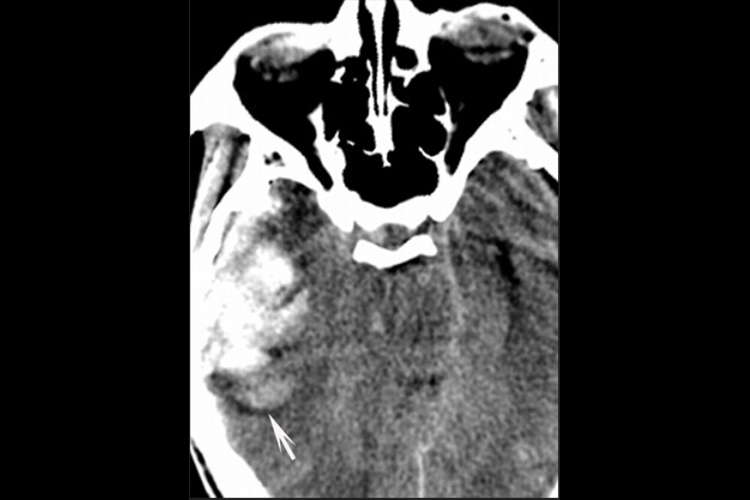

脑挫裂伤:CT平扫显示低密度脑水肿区内,散布斑点状高密度出血灶,伴有占位效应,也可表现为广泛性脑水肿或脑内血肿。